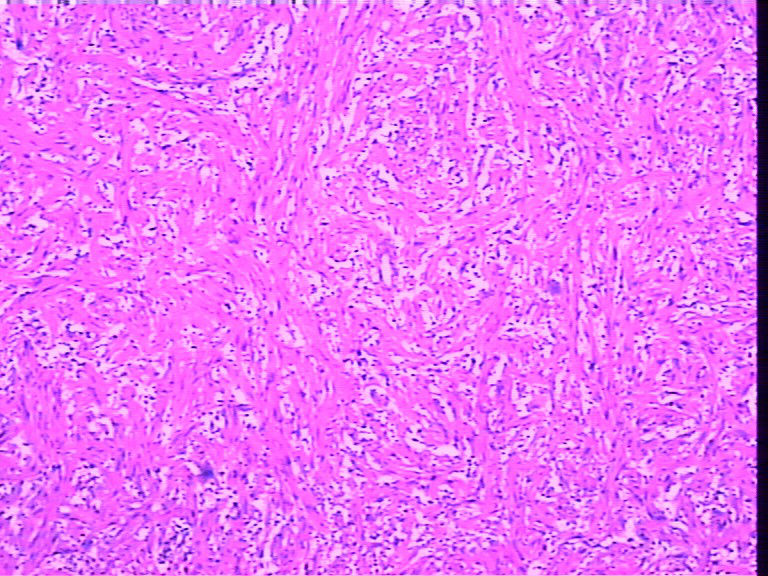

腹壁一个包块,大小4cmx2cmx2cm,椭圆形,有菲薄包膜,淡黄色,切面淡黄色半透明,质地偏韧。

是女性患者,19岁。考虑为神经方面肿瘤,等着病人过来加做免疫组化。